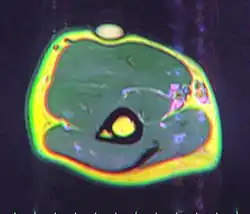

A physical exam is typically the easiest way to diagnose it. Rarely, a tissue biopsy or imaging may be required. The imaging modality of choice is magnetic resonance imaging (MRI) because it has superior sensitivity of distinguishing it from liposarcoma as well as mapping the surrounding anatomy.[22]

MRI showing lipoma of the arm

MRI showing lipoma of the arm -